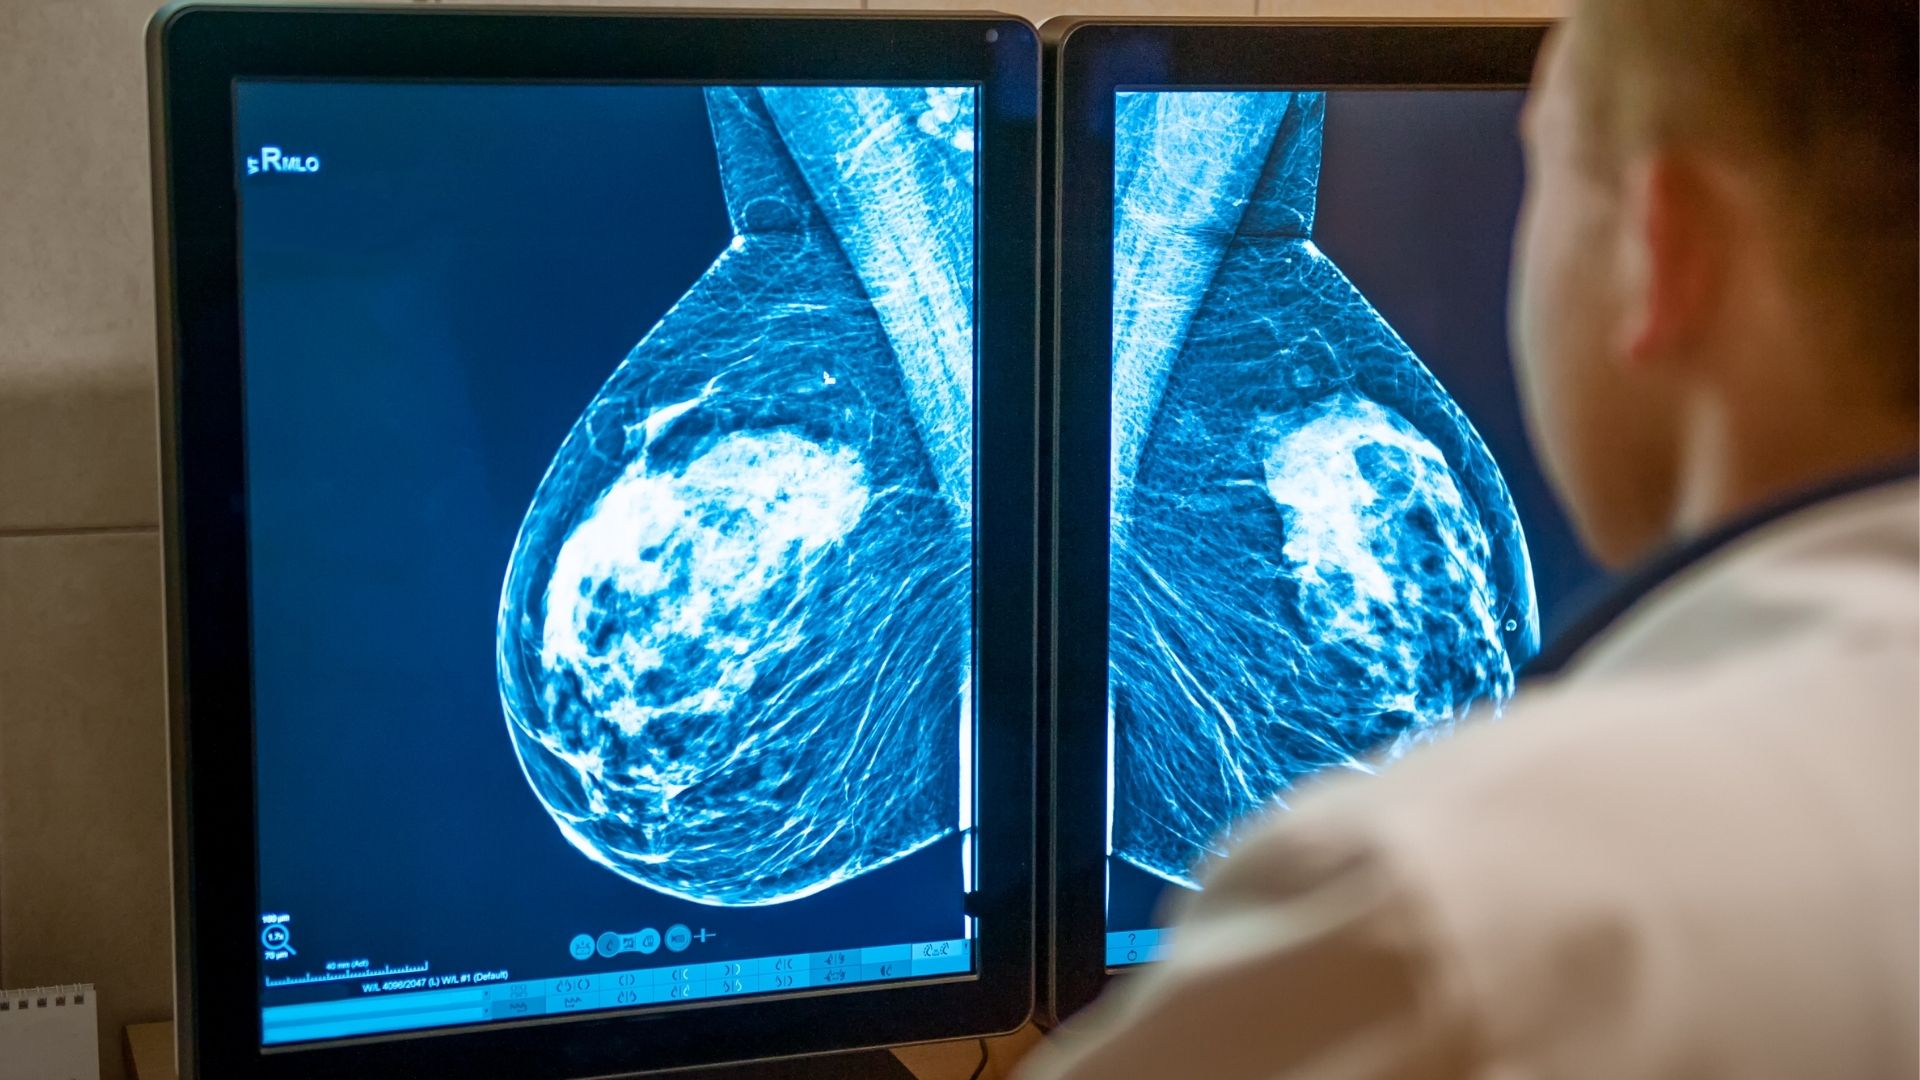

Breast Imaging: 4th edition | Bonnie N. Joe | ISBN。Radiology–pathology correlation of hormonal subtypes of。Breast Imaging (The Core Requisites): 9780323051989。マンモグラフィーや超音波などの診断技術を網羅した、拡大改訂版の医学書。。41mYn2qddfL._AC_SY200_QL15_.jpg。- 書籍名: Diagnostic Breast Imaging- 著者: Sylvia H. Hewayng-Köbrunner, D. David Dershaw, Ingrid Scherer- 版: 第2版, 拡大改訂版- 出版社: Thieme- 内容: マンモグラフィー、超音波、磁気共鳴画像、介入手技に関する情報ご覧いただきありがとうございます。ジュンケイラ組織学 第5版 (原著第14版)